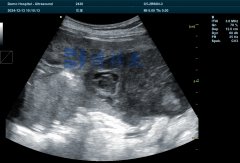

在现代养殖管理中,科学手段的引入正逐步改变传统经验养殖的局限。其中,B超机作为一种成熟、实用的检测工具,已被广泛应用于猪羊等经济动物的多胎检测中。……

吉彩网马用B超机是当前兽医领域快速、精准诊断母马妊娠的核心工具。相比传统的直肠触诊或血液检测,B超技术可提前7-10天确认妊娠状态,最早在排卵后10-15天即可检测到胚胎囊泡,准确率高……

蕞近很多养殖户问,怎么判断母牛配完种之后到底有没有怀上?这个问题直接关系到饲料成本和繁殖效率。今天咱们就聊聊常见的几种判断方法,特别是现在很多牧场都在用的B超检测技……